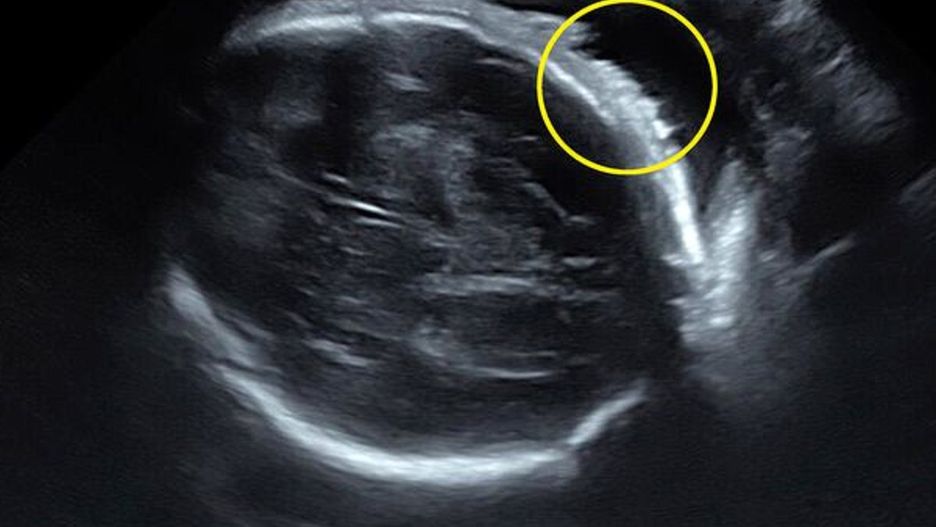

Lekarz wykonywujący badanie USG zatrzymał się na chwilę, ukazując główkę dziecka z profilu. Na jej wierzchołku było widać cienkie białe linie. Lauren początkowo nie wiedziała, na co patrzy, lecz z czasem zrozumiała, że były to włoski jej dziecka.

"Nawet nie wiedziałam, że można zobaczyć włosy na USG – wspomina. – Mówi się, że jak dziecko ma bujną czuprynę, to w czasie ciąży mama walczy ze zgagą. Jednak w moim przypadku nic takiego nie miało miejsca".